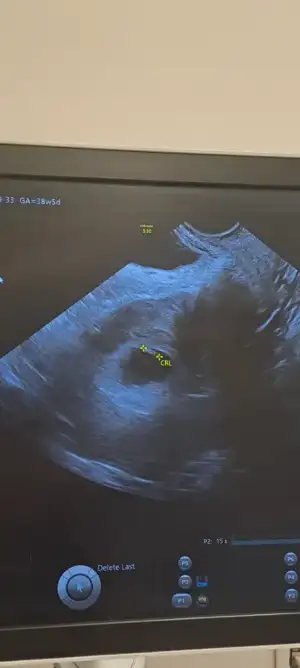

Merhaba 6+3 haftalık hamileyim. Rabbim isteyen herkese nasip etsin inşallah . İlk çocuğumuz elbette her şeyden önce sağlıkla gelsin

. İlk çocuğumuz elbette her şeyden önce sağlıkla gelsin  Ama ister istemez cinsiyetini merak etmeye başladık. Kese, teoriler vs. ye göre cinsiyet tahmini yapabilir misiniz

Ama ister istemez cinsiyetini merak etmeye başladık. Kese, teoriler vs. ye göre cinsiyet tahmini yapabilir misiniz

(Karından görüntüdür)

Not: mavili fotoğraf günceldir. 7+2 haftadan, karından

(Karından görüntüdür)

Not: mavili fotoğraf günceldir. 7+2 haftadan, karından